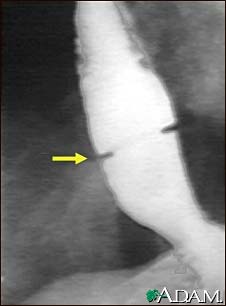

Schatzki ring - X-ray

A solution containing a dye (barium), which is visible on X-rays, has been swallowed (upper GI series) and X-rays have been taken of the esophagus. There is a narrowing near the stomach (indicated by the arrow). This non-cancerous ring of tissue (Shatzki's ring) may cause swallowing problems (dysphagia) and can be treated with dilation of the stricture.